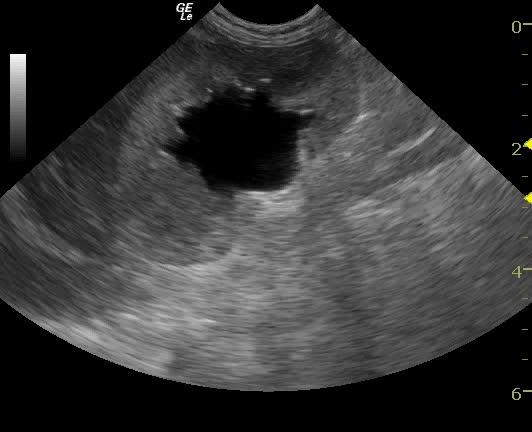

An 11-year-old SF Bichon dog was presented with a history of 3-4 days of lethargy, anorexia, and vomiting. Abnormalities on physical examination were tense abdomen, mild dehydration, and moderate dental tartar. Urinalysis (free-flow sample) showed inappropriate SG, (1.017), hematuria, and, pyuria. Abnormalities on CBC and serum biochemistry were leukocytosis, monocytosis, neutrophilia, azotemia, and hyponatremia.